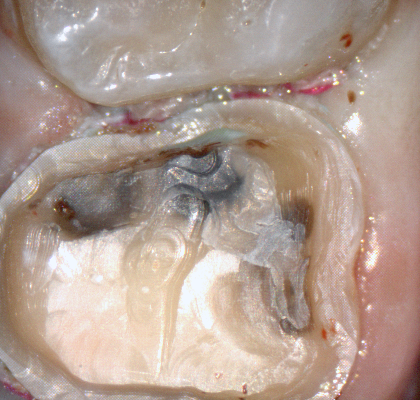

A shoulder bur of .8 mm thickness can help you reduce the interproximal areas as well as the buccal and lingual margin lines. Before finishing the prep, place hemostatic agent like expasyl in the sulcus and place retraction cord. while it is setting, check your reduction. If you need more space, now is the time to reduce some more.

Once you have adequate clearance, retraction, and hemostatis, you can readily image and find your margins in the CAD software